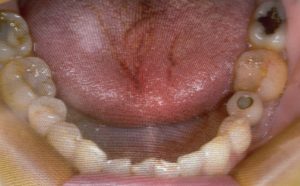

予後32年のインプラント

久しぶりに32年前にオペをした患者さんがいらっしゃいました。自分の一番古い症例です。その当時、インプラント治療は大丈夫なのかと言われていた時代です。今ではどこの歯科医院でもインプラント治療をしているのが嘘のようです。